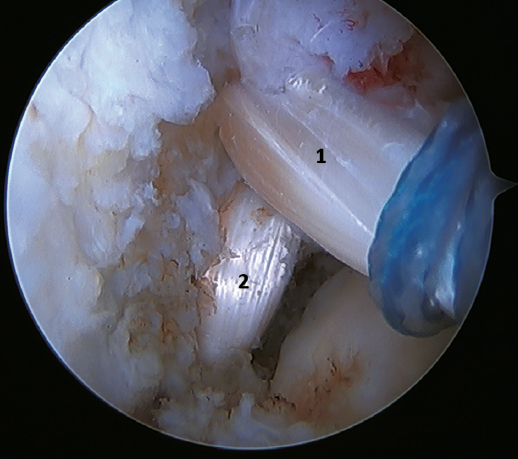

Another point of interest is the presence of os subfibulare. In these cases, we have the option of fixation, although this is usually not feasible and the best therapeutic option is excision and reconstruction, due to the impossibility of direct repair(60) (Figure 4).

A recent consensus(64) recommends reconstruction of the ATFL and CFL (Figures 5 and 6) in cases of generalized laxity or when there is poor tissue quality. Other indications would be when there are doubts about subtalar stability or in patients with a ruptured CFL. For some authors, BMI > 30 kg/m2 would also be an indication for this technique.

In 2022, Ferkel(30) published the indications for reconstruction: failure of ligament repair, BMI > 30 kg/m2, cases of generalized laxity, athletes or workers with a high functional demand, and cases where poor tissue quality is observed intraoperatively. Another indication is when there is significant instability with a talar tilt angle difference of over 10° with respect to the contralateral ankle, or an absolute angle of more than15°. In the same paper, this author concluded that direct arthroscopic repair of the ATFL is an excellent technique in selected cases.

Figure 6. Arthroscopic view of a dual allograft reconstruction of the anterior talofibular ligament (1) and the calcaneofibular ligament (2), showing correct tension and positioning of the fascicles.